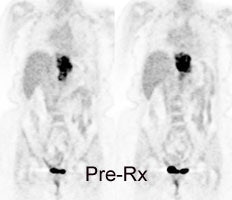

Esophageal carcinoma: The patient shown below presented with a history of progressive dysphagia. A barium swallow revealed a distal esophageal mass. CT and FDG PET imaging were performed for patient staging. The large esophageal mass (white arrows on CT) demonstrated intense tracer uptake (black arrows on PET scan). Uptake could also be seen in regional gastrohepatic ligament nodal metastases (right images). Retrocrural metastases seen on CT blended imperceptibly with the primary tumor on PET imaging. The was no evidence of distant metastatic disease. (Click here to view rotating volume image [1.5 MB])